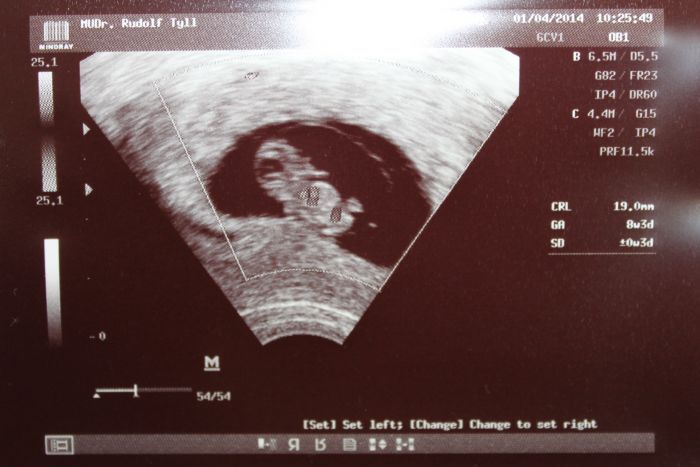

[502611] Jojo, říkal i doktor. Já mu říkám, že tohle těhu je úplně jiný, než to předchozí a že mi pořád bolí to břicho a on na to...ale miminku se daří skvěle :-)...tak to je nejdůležitější :-)

Verca30, v kolikatem tydnu jste? Mimi je krasne videt to snad neni ani mozne.ja zacinam 7tyden a pred tydnem nemela v deloze vubec nic.zitra me ceka kontrola tak jsem zvedava zda mimi bude tam kde ma a pujde videt.

Verčo, ta fotka je náááádherná! To je veliký mimi

tak proti mé první fotce to je mazec teda....gratuluju!!!!!

Ahojky holky, no nás teda je

, super. Veru krásná fotečka, tak my tak krásnou nemáme, protože paní dr. říkala, že není tak kvalitní ultrazvuk, ale to nevadí, taky máme krásné ručičky a nožičky a koukal -la na nás, ale moc se nechtěl -a fotit, vážně na té fotce, co bych dala neuvídíte nic moc. Dneska jsem se již objednala na sreecining jdu 23.4. hned na osmou, 15.4. mě čekají odběry u své dr. a když bude vše v pořádku, dostanu i průkazku, takže teď už se nijak nestresovat.